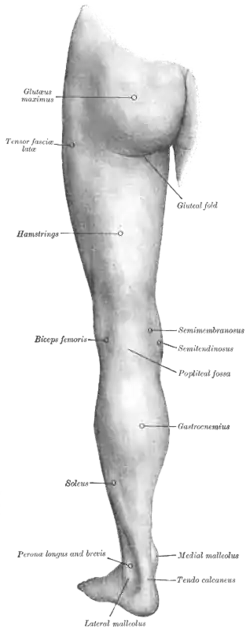

The left leg, with the medial malleolus labeled at bottom right. | |

Each leg is supported by two bones, the tibia on the inner side (medial) of the leg and the fibula on the outer side (lateral) of the leg. The medial malleolus is the prominence on the inner side of the ankle, formed by the lower end of the tibia. The lateral malleolus is the prominence on the outer side of the ankle, formed by the lower end of the fibula.

Medial malleolus

The medial malleolus is found at the foot end of the tibia. The medial surface of the lower extremity of tibia is prolonged downward to form a strong pyramidal process, flattened from without inward - the medial malleolus.

The major structure that passes anterior to the medial malleolus is the saphenous vein.

Structures that pass behind medial malleolus deep to the flexor retinaculum:

The lateral malleolus is found at the foot end of the fibula, of a pyramidal form, and somewhat flattened from side to side; it descends to a lower level than the medial malleolus.

A major structure that is located between the lateral malleolus and the Achilles tendon is the sural nerve.